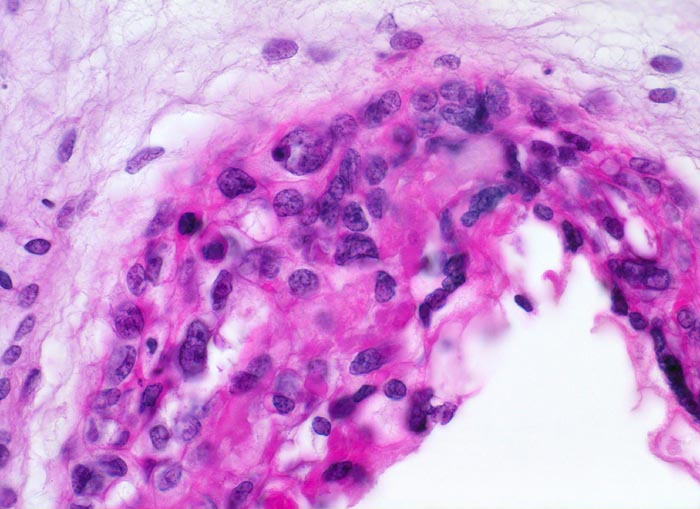

Makroskopisch ist die Plazenta deutlich grösser als erwartet für das Schwangerschaftsalter. Sie ist diffus von bis 2cm grossen Zottenblasen durchsetzt, welche nach Kollaps jedoch der makroskopischen Entdeckung entgehen können. Beim Aufschwemmen in Flüssigkeit entfalten sich die Blasen wieder. Mikroskopisch sind die Zotten aufgrund einer grobblasigen pseudozystischen Hohlraumbildung im Zottenstroma überwiegend grosskalibrig. Im Zottenstroma sind nur ganz vereinzelt Kapillaren nachweisbar. Im Gegensatz zu hydropisch geschwollenen Zotten im Sinne eines Regressionsphänomens zeigen die Zotten bei Blasenmole zusätzlich eine zirkumferentielle Hyperplasie von Synzytio- und Zytotrophoblast mit fakultativer Zellatypie. Bei herdförmiger Mole (> 3725) sind diese Veränderungen nur in einem Teil der Plazentarzotten ausgeprägt.

• Stark vergrösserte und verplumpte Plazentarzotten.

• Hydropisch umgewandeltes Zottenstroma ohne Gefässe mit Ausbildung von pseudozystischen Hohlräumen (Blasen)

• Trophoblastinklusionen und Kerntrümmer im Zottenstroma.

• Überschiessend proliferiertes Trophoblastepithel, teils in der gesamten Zirkumferenz der Zotten mit deutlichen Kernatypien. Kein Embryo.